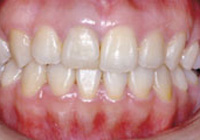

症例1:乱杭歯「歯並びが乱れている」

治療前

治療後